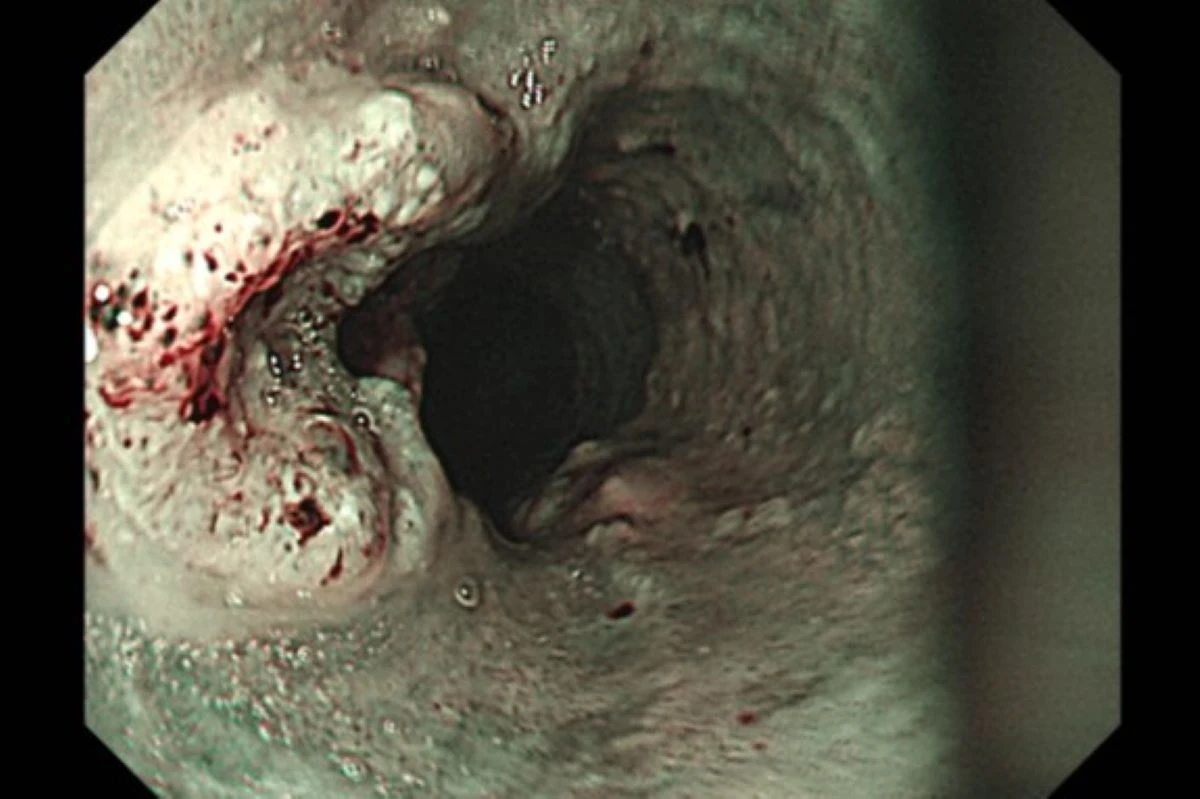

食道癌該如何診斷?洪嘉聰表示,胃鏡檢查是診斷食道癌最常見的方法,可直接觀察腫瘤並切片確認,並搭配電腦斷層、全身骨掃描、腦部磁振造影、全身正子攝影評估轉移情形。

胃鏡檢查是診斷食道癌最常見的方法,左側突起處為食道癌病灶。(圖片來源:台北慈濟醫院)